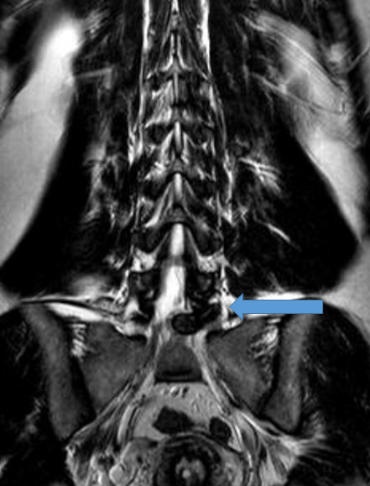

Hernia de disco lumbar extrusa L5 S1 (cortes axiales mostrando

gran compresión sobre la raíz nerviosa izquierda del segmento)

Hernia de disco lumbar extrusa L5 S1 (cortes axiales mostrando gran compresión sobre la raíz nerviosa izquierda del segmento)